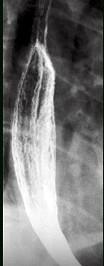

问题 男,34岁,胸骨后烧灼痛1周,伴吞咽痛,餐后平卧时加剧,食管钡餐检查如图,应诊断为 ( )

选项 A.食管癌 B.贲门失弛缓症 C.反流性食管炎 D.食管静脉曲胀 E.正常食管表现

答案 C